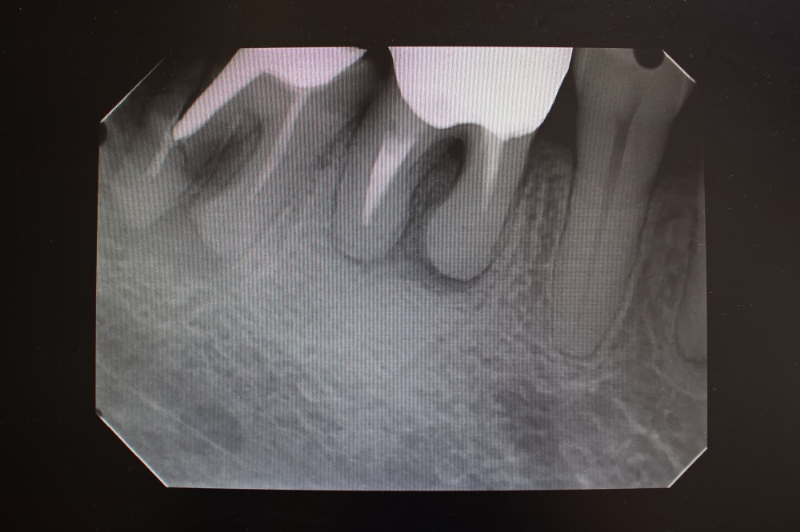

根管治療は、虫歯や外傷などが原因で歯の内部にある神経や血管が細菌に感染したときに行う治療です。歯の内部には歯髄と呼ばれる柔らかい組織があり、そこから細い管状のスペースが歯の根の先まで伸びています。この細い管が根管です。

虫歯が進行して歯髄まで達すると、ズキズキする強い痛みや、噛んだときの痛み、歯ぐきの腫れなどが起こります。そのまま放置すると、感染が歯の根の先や顎の骨にまで広がり、最終的には抜歯が避けられなくなることもあります。

根管治療では、感染した歯髄や細菌を根管の中から取り除き、内部を丁寧に清掃・消毒したうえで、薬剤や材料を詰めて密閉します。こうすることで、細菌が再び入り込むのを防ぎ、歯を抜かずに残せる可能性を高めます。

最初の受診では、問診や視診、レントゲン撮影などを行い、歯の状態や根管の形、感染の広がりを確認します。必要に応じて、歯の周囲の歯周組織の状態などもチェックします。